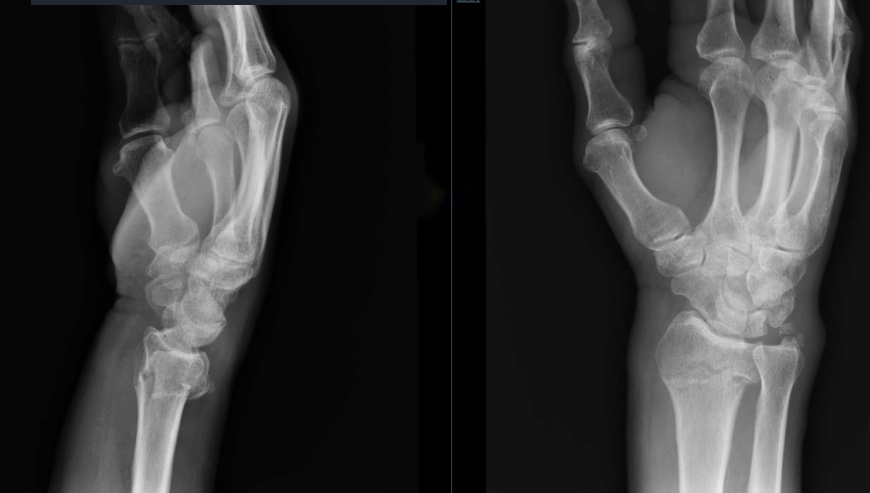

What’s the diagnosis? Gepost op 2 april 202118 maart 2021 door netwerkvsseh What’s the diagnosis? By Dr. Karen O’Brien @emdaily.cooperhealth.org Dit delen: Delen op X (Opent in een nieuw venster) X Share op Facebook (Opent in een nieuw venster) Facebook Delen op LinkedIn (Opent in een nieuw venster) LinkedIn E-mail een link naar een vriend (Opent in een nieuw venster) E-mail Afdrukken (Opent in een nieuw venster) Print Vind-ik-leuk Aan het laden... Gerelateerd